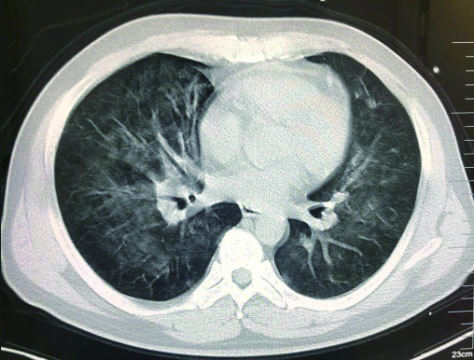

该患者入院后因氧合不能维持、呼吸窘迫直接从急诊收治ICU,大剂量激素冲击及气管插管,呼吸机SIMV+PS模式支持治疗,氧合指数改善不明显,及时行俯卧位通气,但氧合指数仍然小于100,PAO2 38 mmHg, SpO2 78%左右,考虑患者病情危重,且血流动力学不稳,血管活性药剂量大,当天下午行V-V模式ECMO治疗(右侧颈静脉-右侧股静脉),血流速度3.5 L/min,氧流量3.5 L/min,氧体积分数50%,行保护性机械通气,通气模式是压力控制(PC 15 cmH2O,PEEP 8 cmH2O,FiO2 50%,f 12次/min), 镇痛镇静,RASS评分在-4~-5分,必要时阿曲库铵静脉推注行肌肉松弛治疗。其他治疗:甲强龙500 mg治疗3 d,然后逐渐减量;乙酰半胱氨酸抗氧化、化痰、CRRT等支持治疗。ECMO治疗后生命体征明显改善,治疗第2天,血管活性药逐渐减量。治疗3 d后,循环稳定,停用血管活性药,床旁胸片提示:两肺弥漫渗出性改变,较前明显好转。患者症状好转,调节ECMO参数:血流速3 L/min,气体流速3 L/min,氧体积分数35%,控制SpO2 95%~100%之间。在ECMO治疗期间根据血流动力学和血气分析结果不断调整ECMO参数,在ECMO治疗5 d后,脱离ECMO,通气模式改为SIMV+PSV并过渡到PSV(PS 16 cmH2O,PEEP 5 cmH2O,FiO2 30%),氧合良好,在脱离ECMO 2 d后停呼吸机,停机1 d后拔除气管插管。行胸部CT检查示:两肺散在炎性病变,双侧胸膜腔积液(图 3),床旁胸片提示两肺炎性病变(图 4),两肺弥漫性渗出明显改善。后经1周治疗,查胸部CT示:右肺中下叶及左肺少许慢性炎性改变(图 5),病情稳定转至呼吸科病房。

| 图 5 3月26日胸部CT |